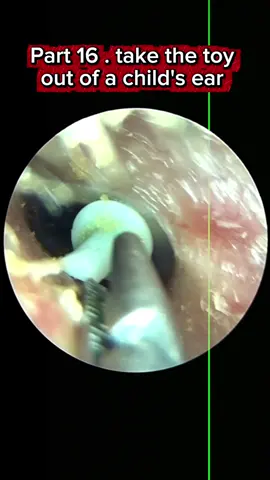

Part16 take the toy out of a child's ear #tiktokawardsusa2025 #earcleaningasmr #satisfyingasmrtingsounds #earwax #tiktokawards